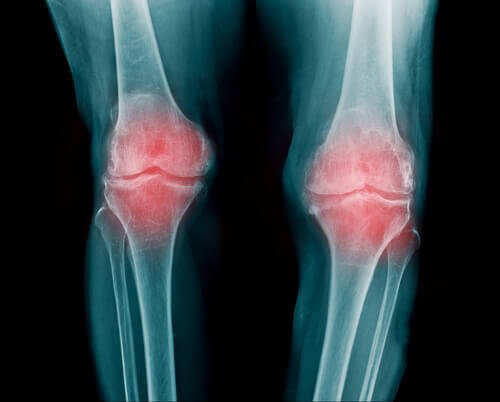

En led är ett område där två eller fler skelettben, alltså ben eller brosk, möts. De ger din kropp rörlighet. Enkelt förklarat får de dina armar, ben och rygg att böja och vrida sig. Mellan benen som leden består av finns det ett flexibelt, elastiskt material; ledbrosk. Brosk motverkar friktion mellan benen och fungerar som en barriär eller kudde.

Leden är omgiven av en ledkapsel som stöder uppbyggnaden. Det i sin tur stöds av ledband som hindrar dina leder från att lätt bli skadade.

- Reumatoid artrit är en inflammation av leden. Den kan påverka flera olika leder. Det är vanligast i fingrar, armar och knän.